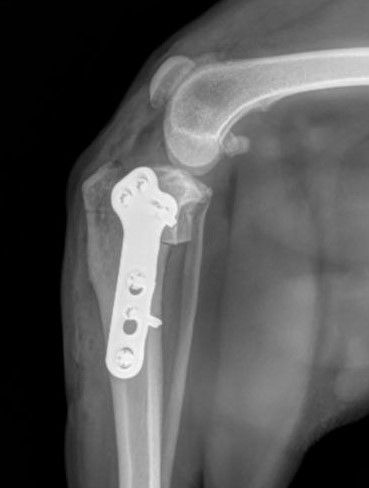

TPLO Tibial Plateau Leveling Osteotomy

Restore Your Dog's Mobility with TPLO Surgery

TPLO: A Game-Changer for Canine Cruciate Ligament Injuries

TPLO surgery has revolutionized the treatment of cruciate ligament injuries in dogs. Here's why your furry companion might benefit from this procedure: